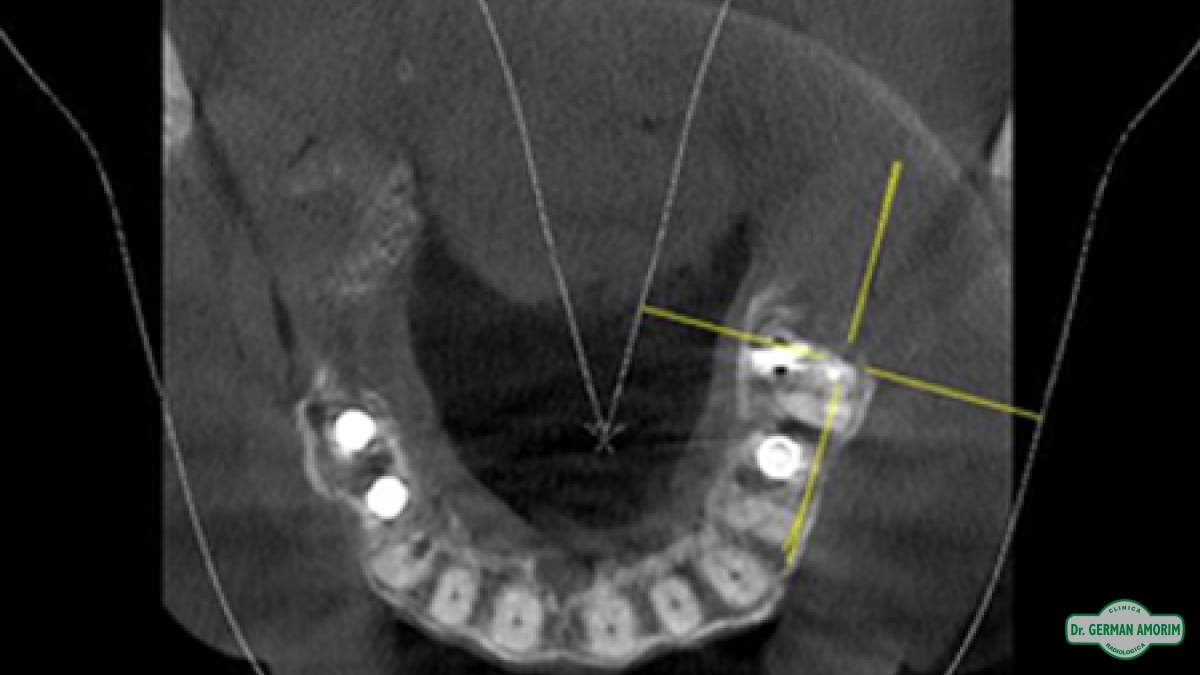

Actualmente y con todos los conocimientos científicos que existen sobre las técnicas implantológicas se recomienda tener siempre una imagen 3D, también en los casos que sea un solo implante. Porque se debe conocer con precisión el espesor de la tabla vestibular para determinar el pronóstico a largo plazo del implante y la única manera de hacerlo es con una tomografía.

El odontólogo utilizando el software específico Galileos puede observar esta imagen en los tres ejes de un espacio tridimensional y trabajar sobre ella para, entre otras cosas, planificar la colocación de los implantes dentales, lesiones ocultas por superposición en las RX convencionales, etc.

• Evaluar si hay hueso suficiente

• Mediciones para ancho y largo del implante

• Planificación y simulación cirugía de implantes